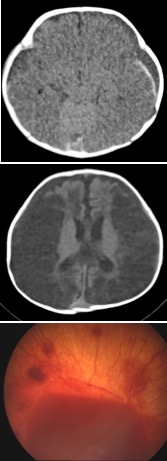

le SBS est défini par l’association d’un hématome sous-dural (HSD), d’hémorragies rétiniennes et d’un oedème cérébral. le diagnostic médical est une urgence, il est le plus souvent simple à condition d’être rigoureux et systématique. il existe en effet des cas atypiques et des diagnostics différentiels qui doivent être systématiquement envisagés ; les questions de datation, de répétition du trauma relèvent de l’expertise médico-légale.

l’hématome sous-dural (HSD)

il s’agit d’une collection hémorragique, présente dès le trauma, mais qui progresse en quelques jours après le trauma, il est alors constitué essentiellement de LCS. Il est typique de l’âge mais pas de la cause du trauma : il ressemble à l’HSD des traumatismes accidentels ; il faut s’attacher à rechercher des signes d’impact, soit compatibles avec le traumatisme invoqué, soit présents en l’absence de notion de trauma (shaken-impact syndrome).

l’oedème cérébral

il s’agit de lésions résultant d’un stress ischémique et non mécanique, dues à l’hypoxémie, l’hypertension intracrânienne avec baisse de la perfusion cérébrale, les crises convulsives avec augmentation du métabolisme cellulaire et excito-toxicité neuronale. les lésions rachis-médullaires contribuent à l’anoxie. C’est un élément de mauvais pronostic, qui heureusement est souvent absent. Il est important de noter que son absence n’exclut pas le diagnostic, et que les cas les moins graves doivent être eux aussi diagnostiqués, sous peine de récidive souvent fatale.

les hémorragies rétiniennes diffuses

il s’agit d’un élément capital du diagnostic. il est important que l’examen soit fait par un ophtalmologiste entraîné, qui sache grader l’hémorragie, et dans des délais courts car les hémorragies peuvent régresser en quelques jours.

le Dr DeFoort-Dhellemmes a proposé un grading des hémorragies rétiniennes :

- type 1: en flammèche, pas toujours traumatique

- type 2: en perle jacobine, traumatique mais pas spécifique de la maltraitance

- type 3: diffuse ; 3A : semis jusqu’en périphérie, 3B en dôme, rétinoschisis : spécifique de la maltraitance sous réserve de traumatisme oculaire direct